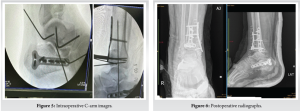

A third-generation cephalosporin was administered for prophylaxis during the induction of general anesthesia. The patient was first placed in a floppy lateral position for reconstruction of the calcaneal fracture. The surgery was performed under tourniquet hemostasis, and a lateral approach was used. A full-thickness subperiosteal flap was raised and reduced with Kirschner wires. The fracture was stabilized with a Locking T plate and screws. Subsequently, the tourniquet was released. Closure done with 2-0 Ethilon and mini VAC kept. The tourniquet was reinflated. The pilon fracture was exposed through an anteromedial incision, with care taken to minimize soft-tissue dissection. The fracture was reduced temporarily with K wires and fixed with an AO cruciate locking T plate and LC DCP Plate and screws. Cancellous bone graft was harvested from the ipsilateral iliac crest to support the articular surface (Fig. 5). Closure was done with 2-0 Ethilon. Below Knee- Back slab applied.

Postoperative radiograph (Fig. 6) showed stable fixation.